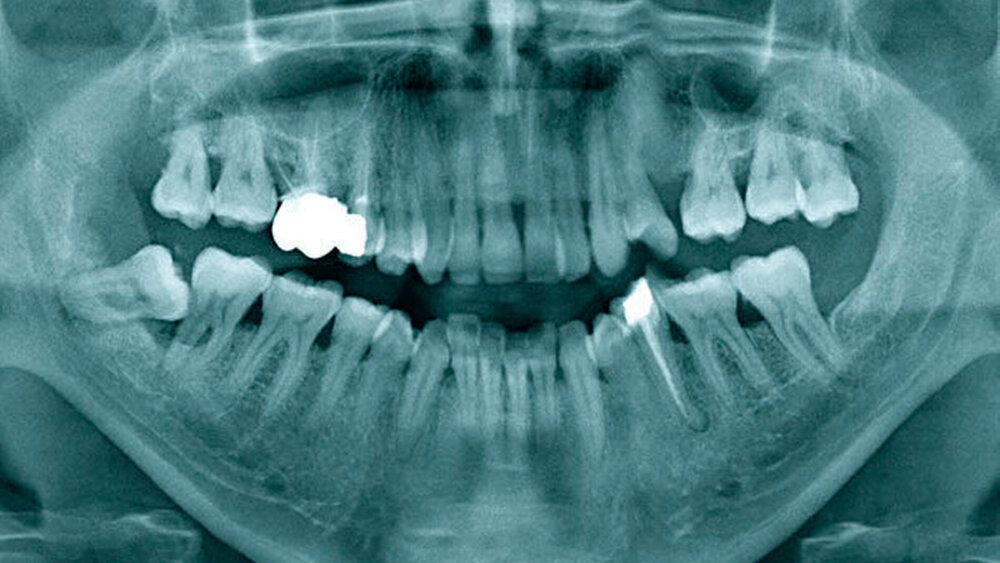

Ein 41-jähriger Mann wurde bei seinem behandelnden Zahnarzt mit einer lokalen Schwellung der Schleimhaut in regio 48 vorstellig. Zudem beklagte er die Lockerung seiner Backenzähne im rechten Unterkiefer. Nach Anfertigung einer Panoramaschichtaufnahme (Abbildung 1) vermutete der Hauszahnarzt mehr als nur eine Perikoronitis am teilretinierten Weisheitszahn 48 und entnahm eine Gewebeprobe. Es erfolgte die histologische Sicherung und Erstdiagnose eines Myxofibroms. Zur weiteren Abklärung und zur Übernahme der Therapie wurde der Patient in die Mund-, Kiefer- und Gesichtschirurgie des Universitätsklinikums überwiesen.

Neben Schwellungen, Schmerzen und Funktionseinschränkungen können – wie im Fallbericht – auch erst sekundäre Symptome wie Zahnlockerungen auf den Befund aufmerksam machen; meist handelt es sich jedoch um radiologische Zufallsbefunde. Im Röntgenbild imponieren irregulär begrenzte uni- oder multilokuläre Transluzenzen, die in der Literatur oftmals mit dem Begriff der „Seifenblase“ beschrieben werden. Die Therapie der Wahl sollte aufgrund der hohen Rezidivfreudigkeit des Myxofibroms (bis zu 25 Prozent der Fälle) [Rocha et al., 2009] die vollständige Resektion des Befunds beinhalten, wobei in Abhängigkeit von der Größe und der Lokalisation des Tumors in der Literatur verschiedene Methoden von der Enukleation und Kürettage bis zur Teilresektion des Kiefers mit dessen Rekonstruktion diskutiert werden [Kawase-Koga et al., 2014].